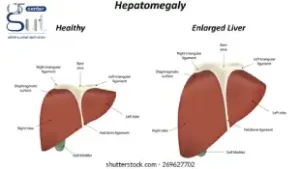

دوالي المريء هي توسعات غير طبيعية في الأوردة الموجودة في جدار المريء، والتي تحدث عادةً بسبب ارتفاع ضغط الدم بالوريد البابي الكبدي الناتج عن أمراض الكبد مثل التليف الكبدي والجلطات.

يعد مرضى التليف الكبدي الأكثر عرضة للإصابة بدوالي المريء بسبب ارتفاع ضغط الدم في الوريد البابي، مما يؤدي إلى تجمع الدم في الأوردة الصغيرة في المريء وتوسعها بشكل غير طبيعي.

تزداد احتمالية تطور درجات دوالي المريء وحدوث مضاعفات خطيرة مثل النزيف كلما زادت نسبة التليف الكبدي وكذلك الجلطات بالوريد البابي الكبدي التي تؤدي إلى حدوث وتطور الدوالي المريئية.

مريض التليف الكبدي المصاب بدوالي المريء يواجه خطرًا حقيقيًا ومعقدًا نتيجة تطور المرض وتأثيره المباشر على الدورة الدموية داخل الكبد. إذ يُعد ارتفاع ضغط الدم البابي أحد المضاعفات الشائعة لتليف الكبد، وهو ما يؤدي إلى تكون دوالي في المريء نتيجة احتقان الدم في الأوردة المحيطة.

وفي الأشخاص الذين تم تشخيص إصابتهم بتليف الكبد، يعاني 30% منهم بالفعل من ارتفاع ضغط الدم البابي ودوالي المريء في وقت التشخيص، وما يصل إلى 90٪ ستطور لديهم خلال السنوات العشر التالية. ومع تفاقم التليف، يزداد الضغط داخل هذه الأوردة، مما يجعل الدوالي أكثر بروزًا وأكثر عرضة للتمزق والنزيف – وهي حالة طبية طارئة تتطلب تدخلاً فوريًا.

- زراعة الكبد: تعتبر الخيار الأخير في الحالات المتقدمة من التليف الكبدي عندما يكون الكبد غير قادر على أداء وظائفه.

تحدث دوالي المريء عادة في المرحلة المتقدمة من تليف الكبد، عندما يؤدي المرض إلى ارتفاع ضغط الدم البابي داخل الكبد.